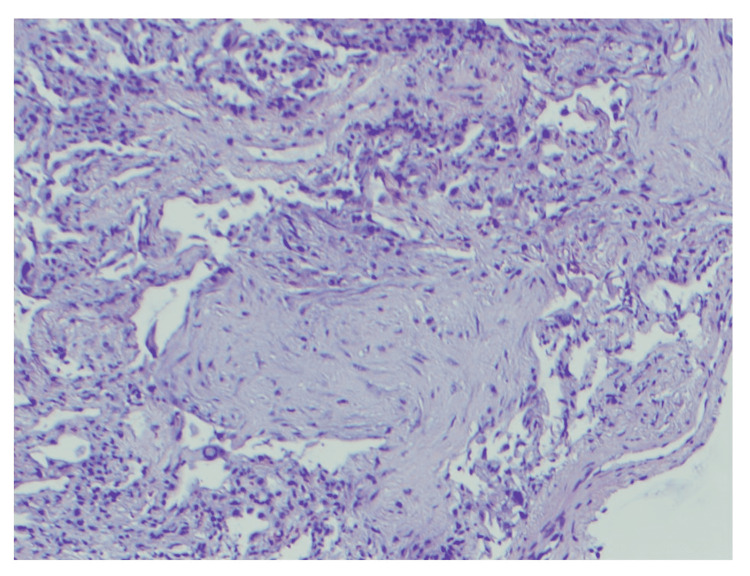

A 19-year-old female with a medical history of seizures and neurocysticercosis status post-stereotactic brain biopsy that was treated in her childhood presented with a complaint of worsening shortness of breath. She endorsed vaping for about two years and denied any drug use. She did not take any medication. Family history and environmental exposure were unremarkable. She had a recent emergency room visit for abdominal pain associated with nausea and vomiting a week prior to admission. On presentation, she was afebrile, with a heart rate of 134 beats per minute, respiratory rate of 16 breaths per minute, and blood pressure of 121/68 mmHg. Scattered end-expiratory wheezing and mild diffuse rhonchi were noted on auscultation. She denied any sick contacts. Chest X-ray demonstrated multifocal bilateral opacities (Figure 1), and labs were remarkable for a white blood cell (WBC) count of 13.8 K/µL. Rapid influenza was negative. She was empirically started on ceftriaxone and azithromycin for community-acquired pneumonia (CAP). Hypoxemia progressed and she required intubation, followed by mechanical ventilation. An echocardiogram revealed a normal left ventricular ejection fraction of 65-70%. Multiple blood cultures, sputum, and tracheal aspirate cultures, as well as a workup for atypical infections, including fungal and mycobacterial infections, were all negative. Human immunodeficiency virus (HIV) and immunoglobulin levels were unremarkable, and there was no evidence of an immunocompromised status. Vasculitis and connective tissue disease workup were negative as well. The patient underwent bronchoscopy with bronchoalveolar lavage (BAL) which showed only neutrophilic alveolitis (BAL had 1,075 red blood cells (RBCs) and 557 WBCs with a differential of 53% neutrophils, 35% monocytes, 10% lymphocytes, and 2% eosinophils). A surgical lung biopsy of the left lower lobe was performed. She finished a seven-day course of antibiotics (cefepime, levofloxacin, and linezolid) and was extubated two days after the open lung biopsy that revealed diffuse interstitial fibrosis associated with type 2 pneumocyte hyperplasia and patchy organizing pneumonia suggestive of acute lung injury and nonspecific interstitial pneumonia (NSIP) (Figure 2). NSIP can be one of the outcomes of acute lung injury.